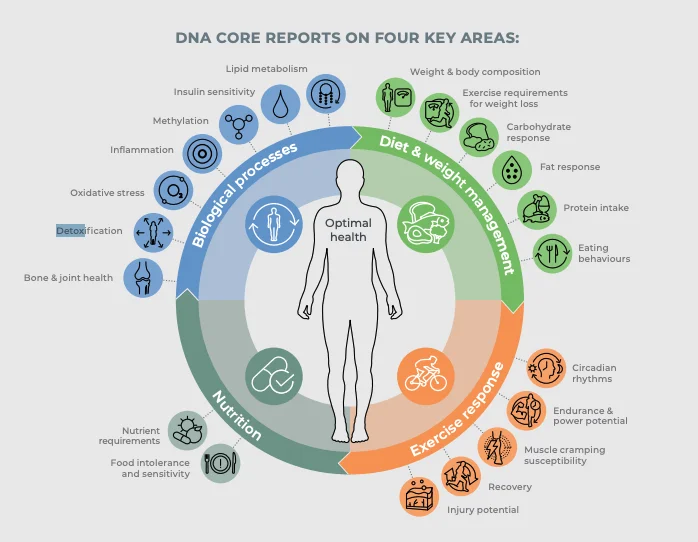

We offer five key tests to see what groups you fall into. These genes are known to affect:

Your individual sensitivity to anabolic steroids

AR - CAG repeats

How fast your body naturally breaks down steroids

CYP3A4*22

Your ability to convert androgens (male hormones) to oestrogens (female hormones)

CYP19A1

Your natural ability to excrete steroids

UGT2B17

Your ability to convert testosterone into a more active hormone.

SRD5A2

FEATURES

Get yourself checked today.

Learn what your DNA tells you about your androgen response risks

based on your genes, using the latest scientific research.

Complete Panel

Get all 5 tests with a consultation for the most comprehensive hormone genetics analysis available.